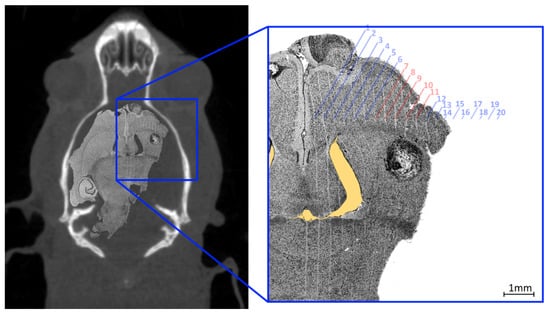

For histological analysis, a rat was euthanized with an intraperitoneal injection of lethabarb 14 days after MRT, using a 325 mg/mL solution to a dose of 800 mg/kg, according to Engels et al. [30]. The brain was collected by removing the skull and placed immediately in 10% neutral buffered formalin for fixation. Fixed brains were sliced transversely, processed through graded alcohols and xylene, embedded in paraffin, to obtain 4 μ m sections. These sections were stained with haematoxylin and eosin. Histology images were acquired using a Leica DMI4000 B Inverted Microscope using multi-step (tiled) image acquisition with light field corrections applied presented in Figure 10.

The curved appearance of some of the microbeams tracks, particularly due to towards the middle third of the treatment field is a results of physical deformation such as manual handling of the histology slice during slide preparation and dehydration of the sliced sample. The yellow shaded region highlights a void in the brain material caused by manual handling of the fragile tissue. These deformations remove the ability to accurately spatially calibrate the image however, the known field properties may be used to investigate alignment accuracy. The 8 mm × 8 mm MRT treatment field used to treat the imaged animal (bearing a 1.50   m m 3 tumour) consisted of 20 microbeams ( 50 μ m FWHM, 400 μ m pitch) the centre of such field lying between microbeams 10 and 11. The histology image shows the tumour at 7 m m depth enveloped by microbeams 7 to 11 of the treatment field; with the tumour at this depth not representative of the centre of mass targeted during treatment. Confirmation of accuracy here supports the potential reduction of the treatment field size for future work.

Figure 10. Composite image with a histology slide overlaid on corresponding coronal CT slice of tumour-bearing rat, 14 days after MRT treatment (left). The enlarged image (right) shows a tumour situated within the MRT treatment field (parallel vertical lines) with microbeams present and expected numbered with red text identifying the microbeams that transit the tumour mass (dark circular object at the centre of the frame). The yellow shaded region highlights a void in the brain material caused by manual handling of the fragile tissue.